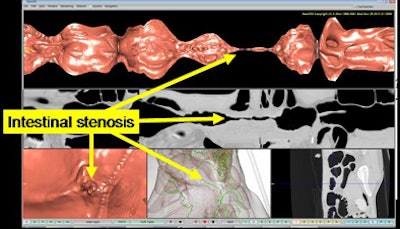

The CAD system displays five views of the intestine simultaneously, including a virtual unfolded view, virtual endoscopic view, curved planar reconstruction view, multiplanar reconstruction view, and the outside wall of the intestine, Oda said.

The display indicates intestinal stenosis by changing the height of the virtual unfolded view, and it enhances longitudinal ulcers via concave region enhancement, Oda said.

| Virtual endoscopy display shows five different views of the intestinal tract on a single screenshot, including (clockwise from top) virtual unfolded view, curved planar reconstruction view, multiplanar reconstruction view, outside view, and virtual endoscopy view. Unfolded view (top arrow) shows stenotic narrowing, which is further characterized by curved planar reconstruction (middle arrow) and virtual endoscopy (bottom arrow) views. All images courtesy of Masahiro Oda. |

"We observed the intestines of 11 fecal-tagging abdominal CT images using the system," he said. "Changing the height of virtual unfolded views enabled intuitive understanding of positions of intestinal stenosis. In addition, the virtual endoscopy, curved planar reconstruction, and multiplanar views permitted close inspection of the intestinal wall."